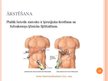

Žultspūšļa un žultsceļu ķirurģiskās slimības